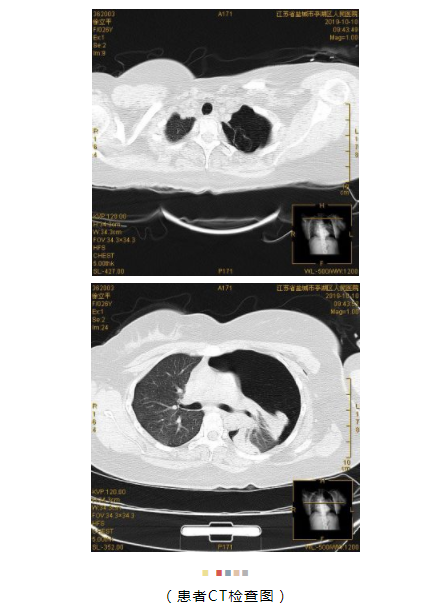

患者,女,26岁,身材中等,近日,突感胸闷、胸痛,在我院行胸部CT检查示:左侧气胸(左肺组织压缩约95%)。

入院后即行左侧胸腔闭式引流等急诊治疗,症状缓解,后行胸部CT检查发现:左上肺多发肺大泡且有束带粘连。此次气胸发作考虑为肺大泡破裂所致且后续有粘连束带断裂导致胸腔出血可能,遂建议患者行手术治疗。